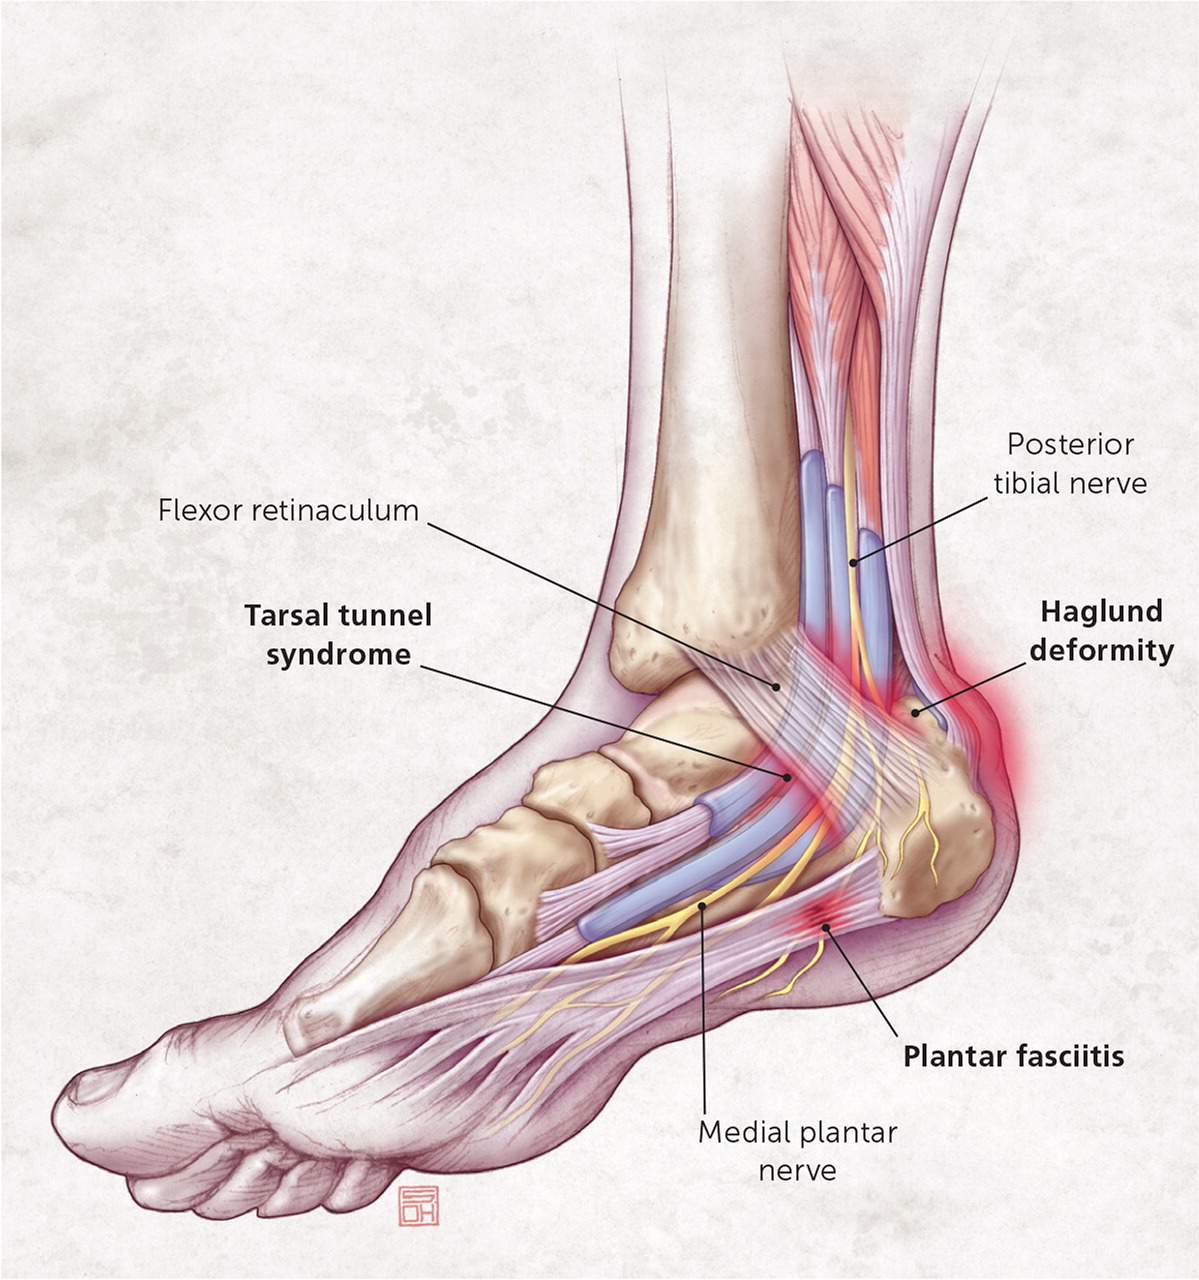

Heel Pain Diagnosis and Management AAFP

Posterior heel pain Chelsea and Westminster Hospital NHS Foundation Trust

Heel Bursitis Demystified Symptoms and Solutions

Posterior Heel Spur Diagnosed Treated by Foot Surgeons Mercy in Baltimore

Bone spurs of the heel of foot defined and treatments